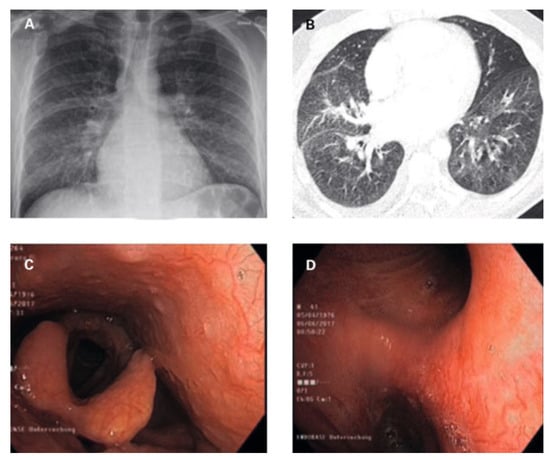

On admission, the patient’s blood pressure was 127/77 mm Hg, heart rate was 97/min, and oxygen saturation was 98% while breathing ambient air. On physical examination, discrete wheezing on pulmonary auscultation and slight oedema of the legs were found. Cardiac auscultation was remarkable for a holosystolic murmur and a rumbling diastolic murmur, both best heard in the apex. The ECG showed sinus rhythm with right axis deviation, inferolateral early repolarisation pattern and a bifid p wave (fig. 1). Chest X-ray showed normal cardiac size and a diffuse interstitial abnormality (fig. 2A). A computed tomography (CT) scan revealed a centrilobular ground-glass pattern of the lung parenchyma and thickened bronchial walls (fig. 2B). There were no other signs indicative for lung cancer, pneumonia, pulmonary embolism or bronchiectasis (fig. 2B).

Bronchoscopy revealed hyperaemic bronchial mucosa with ectatic and tortuous vessels, with a high tendency towards bleeding on contact with the bronchoscope, identified as the obvious source of the recurrent haemoptysis (fig. 2C,D). Broncho-alveolar lavage was remarkable macroscopically for recovery of slight haemorrhagic fluid , and microscopically for a high haemosiderin-laden macrophage count. Leucocyte

Figure 2. Imaging and bronchoscopy findings (description in text).